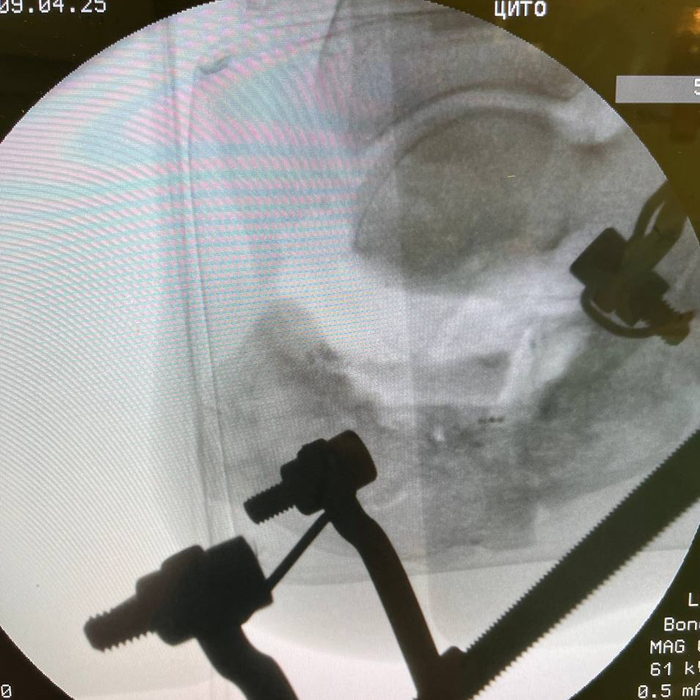

Внешний вид «простого» дистракционного аппарата». Использую фиксацию таран-пятка. Получается хороший вектор дистракции. Еще можно рассматривать вариант с проведением спицы через передний край большеберцовой кости.

Устанавливается спица через шейку таранной кости и через нижний край пяточного бугра. Дуги располагаются таким образом, чтобы они не мешали работать с хирургической раной. Дистальную часть штанги не закреплял гайками для возможности быстрой корректировки положения. Учитывая, что аппарат находится на дистракции, то отсутствие гаек не мешает работе. Обычно, медиальная штанга должна быть короче латеральной. Таким образом мы обеспечиваем варизацию пяточной кости и восстановление ее правильного положения.

Этапный снимок с установкой аппарата.

ЭОП-контроль положения трансплантата. Можете обратить внимание, что окончательная дистракция больше чем была на промежуточных снимках.